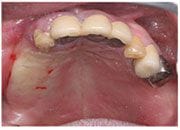

治療前